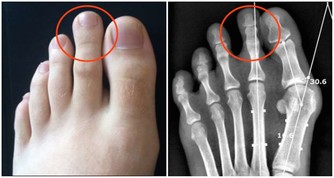

1. 肌肉痙攣

當人體處在缺水狀態時,肌肉無法有效地接受大腦所傳輸的神經信號;腿部肌肉發生這類情況的概率更高,表現症狀便是小腿或大腿抽筋。鍛煉強度過高,沒有及時補充水分時,肌肉中還會出現電解質失衡的情況。如此一來不僅會導致肌肉痙攣,還會增加鍛煉之後出現肌肉酸痛的風險。